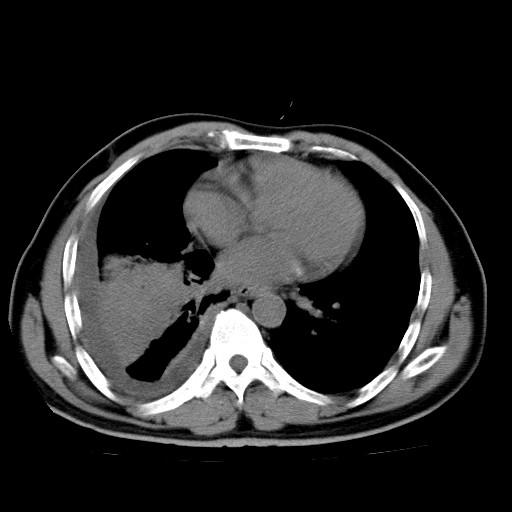

男,54岁,咳嗽,右侧胸痛10天。肺窗>150k,传不了

右中央型肺癌并右肺下叶不张,纵隔内及右胸膜转移,右胸腔积液

考虑   右肺癌伴右下肺部分不张,阻塞性肺炎,纵隔淋巴结增大,右侧胸腔积液其他待排

右下叶大片实变,肺门未见明显肿块影。有胸腔积液和纵隔内肿大淋巴结影。没有增强和肺窗,不好定。

考虑:1、右下叶周围型肺癌伴胸膜、纵隔淋巴转移?

右下叶大片性阻塞性肺炎,肺门未见明显肿块影,纵隔内可见肿大淋巴结影,右见右侧胸腔积液及右侧胸膜增厚。

考虑:右侧中心性肺癌?伴纵隔淋巴结转移。建议上传肺窗。